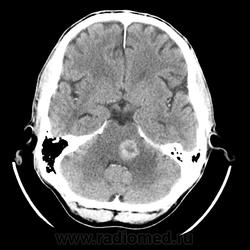

КТ ГМ+C Субтенториальное объемное образование в стволе головного мозга (мост)

Мужчина 46 лет. Поступил с подозрением на ОНМК. Жалобы на шаткую походку, снижение зрения. Мост содержит ядра ЧМН (V, VI, VII, VIII). Для невриномы и менингиомы не  характерна локализация. Узловое, экспансивно растущее образование, интенсивно накапливает КВ. DDs: Кавернозная ангиома, mts.

Да, а контраст то не должна копить, а в случае хронической гематомы только по перифирии.

Да как то не выражен, может незначительный, IV желудочек не резко  деформирован и сужен.

По-моему отека предостаточно.

мост и левая средняя мозжечковая ножка гипо-, цистерн ЗЧЯ вообще не видно...

У Трофимовой " Можно наблюдать КУ" очень размыто написано,  непонятно какое КУ слабо выраженное или интенсивное, гомогеное или гетерогенное? Больше Пронину и Корниенко доверяю, а они утверждают, что либо КУ не определяется, либо слабо выраженный характер, даже точечный.  А в данном случае я не могу сказать, что контраст копит слабо...хорошо так копит, потому и подумал больше в сторону mts. В любом случае  МРТ я порекомендовал.